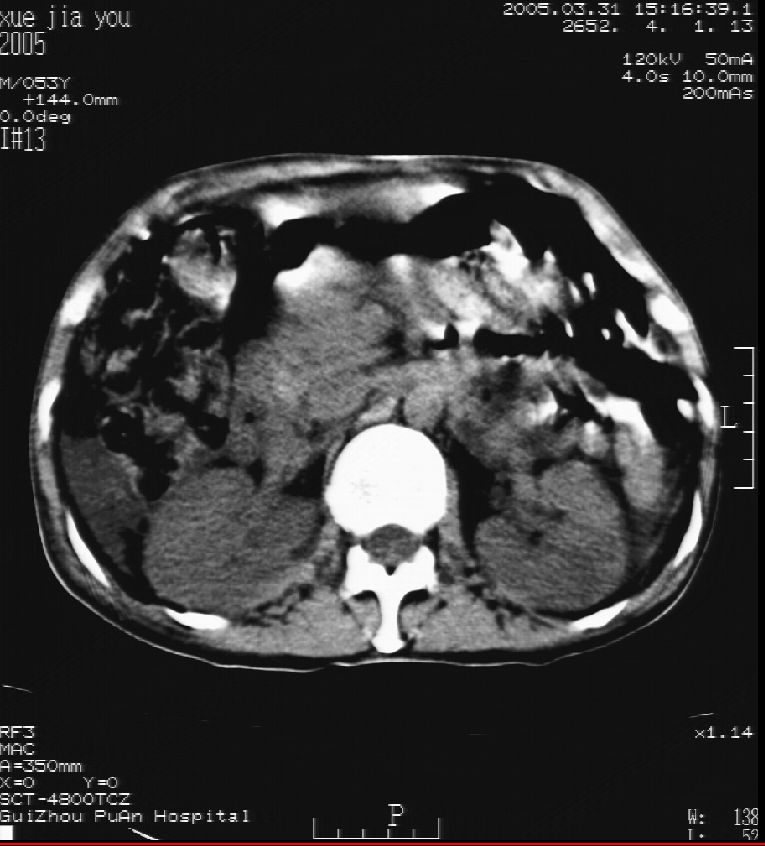

男 55岁  反复上腹痛1年,伴恶心呕吐。2005年做第一次检查后,到外院做b超检查提示肝囊肿,未做任何手术。2006年做过胆总管结石术。骨窗未见异常

这个病灶很有意思,怎么可能没有了呢?我考虑当时很可能是肝脏脓肿(b超示囊肿是有可能误诊的,因为影像表现都是低回声吗?),现在脓肿吸收了,肝脏萎缩,肝裂增宽了.别的肝叶代偿增大,不过现在左内叶的确有个占位,肝内多发结石,脾脏比以前大,不排除有肝硬化可能.建议增强扫描给于定性!!!!

肝硬化\\脾大,肝左叶肝癌可能性大,建议增强扫描.肝内胆管多发性结石.

1, 肝硬化,脾大;2,肝左叶肝癌可能性大,建议增强扫描.3,肝内胆管多发性结石.

考虑肝内胆管多发结石引起的肝内局部炎症,这样可以解释2005年肝右叶病灶的吸收和左叶新病灶.

肝硬化、脾大、肝内胆管多发结石。肝左叶低密度占位。建议增强扫描.排除肝癌